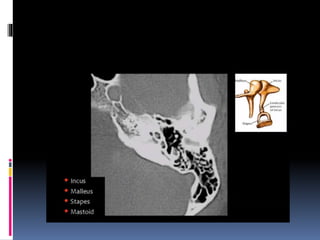

Imaging of the ear

Superior surface of petrous bone

Medial surface of petrous

bone